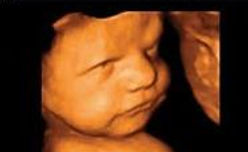

f) Realizar ultrsonido de 3 y 4 D